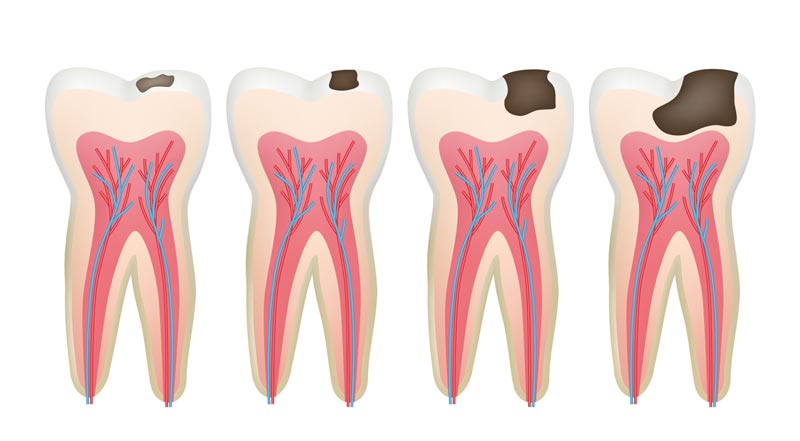

مراحل پوسیدگی دندان

پوسیدگی دندان به صورت ناگهانی رخ نمی دهد، بلکه در چندین مرحله پیشرفت می کند که هر کدام پیامدهای خاصی برای سلامت دهان دارند.

- مرحله اول: دمینرالیزاسیون اولیه

در اولین مرحله، پوسیدگی به صورت لکه های سفید بر روی سطح دندان ظاهر می شود. این لکه ها نشان دهنده از دست رفتن مواد معدنی از مینای دندان بر اثر حمله اسیدی هستند. در این مرحله، پوسیدگی قابل بازگشت است و می توان با درمان های فلوراید، بهبود بهداشت دهان و تغییر رژیم غذایی، از پیشرفت آن جلوگیری کرد.

- مرحله دوم: پوسیدگی مینای دندان

در صورت ادامه یافتن فرآیند دمینرالیزاسیون، مینای دندان شروع به تخریب کرده و یک حفره کوچک تشکیل می شود. از این مرحله به بعد، پوسیدگی دیگر به طور طبیعی ترمیم نمی شود و نیاز به مداخله دندانپزشکی دارد. در این مرحله، حساسیت دندان نسبت به مواد شیرین، گرم یا سرد افزایش می یابد.

- مرحله سوم: پوسیدگی عاج دندان

با نفوذ پوسیدگی به لایه عاج، که نرم تر از مینا و حساس تر به اسیدهاست، پوسیدگی با سرعت بیشتری گسترش می یابد. در این مرحله، فرد دچار حساسیت بیشتر و درد های مقطعی می شود.

- مرحله چهارم: درگیری پالپ دندان

زمانی که پوسیدگی به مغز دندان (پالپ) برسد، التهاب و عفونت رخ می دهد که معمولاً با درد شدید و ضربان دار همراه است. در این مرحله، بیمار ممکن است به درمان هایی مانند عصب کشی دندان یا در موارد شدیدتر، کشیدن دندان نیاز داشته باشد.

- مرحله پنجم: تشکیل آبسه

آخرین مرحله پوسیدگی، تشکیل آبسه در اطراف ریشه دندان است که می تواند منجر به درد شدید، تورم صورت، تب و حتی گسترش عفونت به سایر نقاط بدن شود. در این شرایط، مراجعه فوری به بهترین دندانپزشک تهران ضروری است.